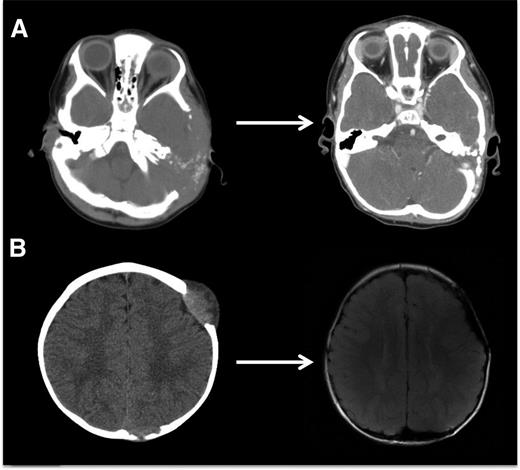

Evaluating disease activity and response to therapy

LCH bone lesions may remodel if margins remain intact. These cases highlight the potential for even very large bone lesions to remodel following disease resolution. (A) Skull CT scans before and after chemotherapy in a patient with multifocal bone LCH. Remodeling following systemic chemotherapy nearly normalizes bone structure in a patient with significant skull lesions. This patient did not have any curettage or excisional surgery in the skull. (B) Brain MRI in a patient with multifocal bone LCH before and after complete excision with placement of mesh grafts. Complete excision of LCH lesion with margins into healthy bone inhibits potential for remodeling. Following resections and successful chemotherapy, skull defects persist.